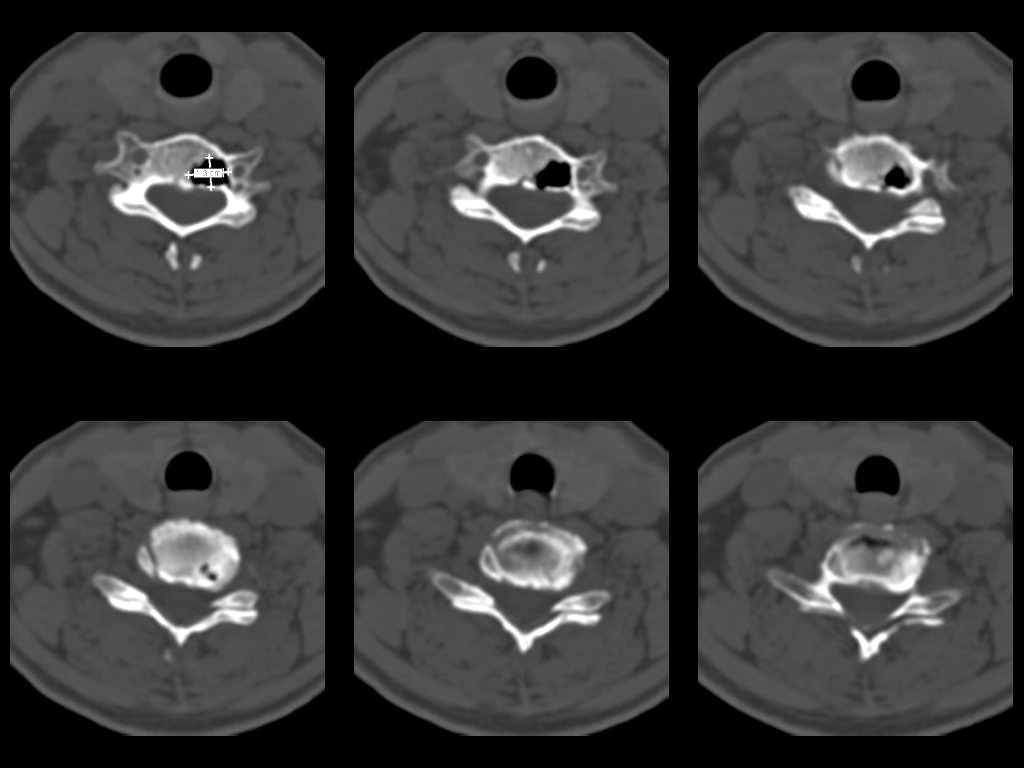

У женщины 49 лет, при рентгенографии шейного отдела в теле С6 выявлен участок деструкции.Часть N1 Больная находилась в неврологическом отделении с диагнозом энцефалопатия. Была проведена КТ тела С6, 26.12.2002 выявлен участок деструкции 0,9х1,2 см, плотность участка составляет -1022 ед.Н. аналогичная плотности воздуха в трахее.Возникает вопрос что это? Метастаз, киста,или какой то вредный анаэроб грызет тело позвонка?Через пол года 03.06.2003 произведено повторное исследование. Отмечается отрицательная динамика. Участок деструкции увеличился в размерах, увеличелась площадь разрушения задней поверхности тела С6.

Наличие выраженных дистрофических изменений, а также сообщение полости в теле позвонка С6 с полостью межпозвонкового диска в сегменте С5-С6, а также наличие газа в полости межпозвонкового диска С5-С6 спереди, на границе фиброзного кольца и пульпозного ядра (3-й слева срез в нижнем ряду на второй из представленных КТ) делает диагноз остеохондроза, осложненного вакуум-феноменом и прорывом газа в полость тела позвонка с формированием воздушной кисты (пневмкисты) несомненным.

Первые 2 серии снимков это от 2002г, вторые 2 серии от 2003 г. Относительно размеров, сообщю дополнительно все перермерю на томографе.

Размеры за 2002 год 1,2х0,9х1,2 мм

за 2003 1,3х0,9х1,2 мм. Но контур деструкции стал более неровный и внедрение в дужку С6 увеличелось.

Характер процесса не вполне ясен. Учитывая скопление газа на фоне тела

позвонка, с наибольшей вероятностью - "вакуум-феномен" в следствии

дегенерации межпозвонкового диска. Наложение газа на образование в теле

позвонка (гемангиома?) создает затруднение в диагностике (по-видимому

сочетание двух процессов). Желательно МРТ исследование. Если возможно,